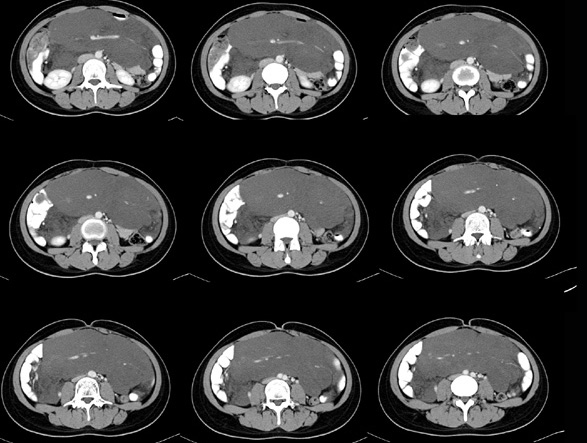

女性,28岁,停经3月,腹部膨隆1月,产前检查发现腹部占位

{肿块中心ct值27hu,增强后,动脉期、门脉期均无明显强化)

患者手术病理:腹腔囊性淋巴管瘤,象这样充满整个腹腔的的确很少见